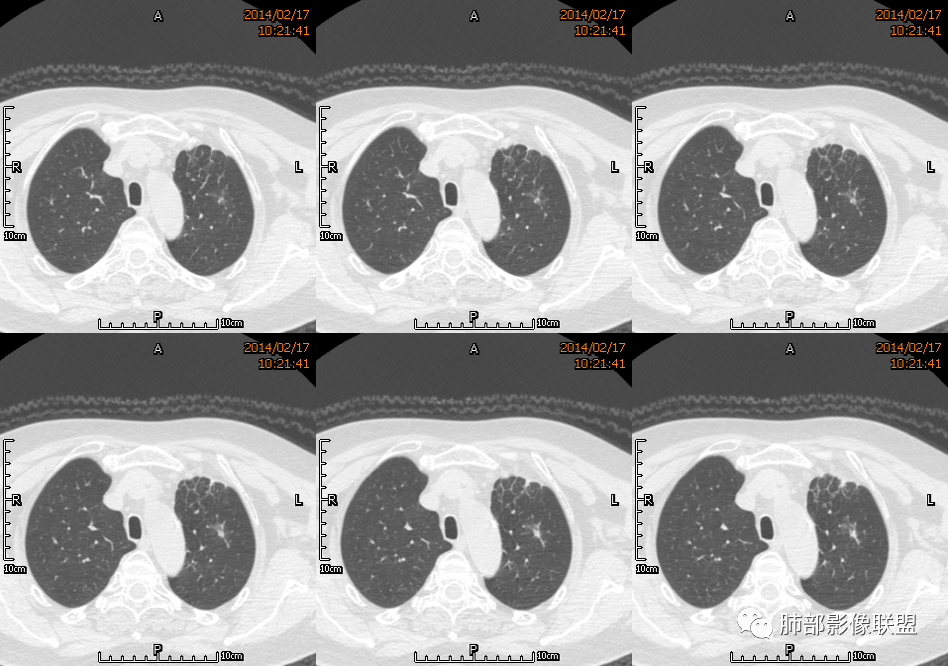

1.老年女性,咳嗽咳痰10天,痰中带血4天。病程较短,临床中毒症状不重。

2.左肺上叶前段胸膜下块状影,不规则呈“逗点样”延向肺门区,边界清楚,未见分叶、毛刺及张力,表面不规则棘突,状如“火焰”或“日冕”。相邻胸膜增厚,未见栽赃、卫星病灶。

3.病灶密度不均,中央坏死液化并见气泡影,支气管及血管贴边进入,较均匀环形强化(显示多层结构),未见明确壁结节。

4.肺门纵隔未见肿大淋巴结。

综合分析:

1.块影不规则,未见分叶、毛刺及张力,未见壁结节,肺门纵隔未见肿大淋巴结等,缺少肺腺癌的特征。

2.未见血管及支气管受累,用肺鳞癌不好解释,何况女性患者。

3.病灶易坏死液化,环形强化,支气管及血管贴边进入,“火焰”样边缘轮廓,更符合炎性块影的特点。

4.单发脓肿,临床中毒症状不重,短期多见于肺炎克雷比杆菌感染,亚急性病程的还应排除奴卡菌感染。